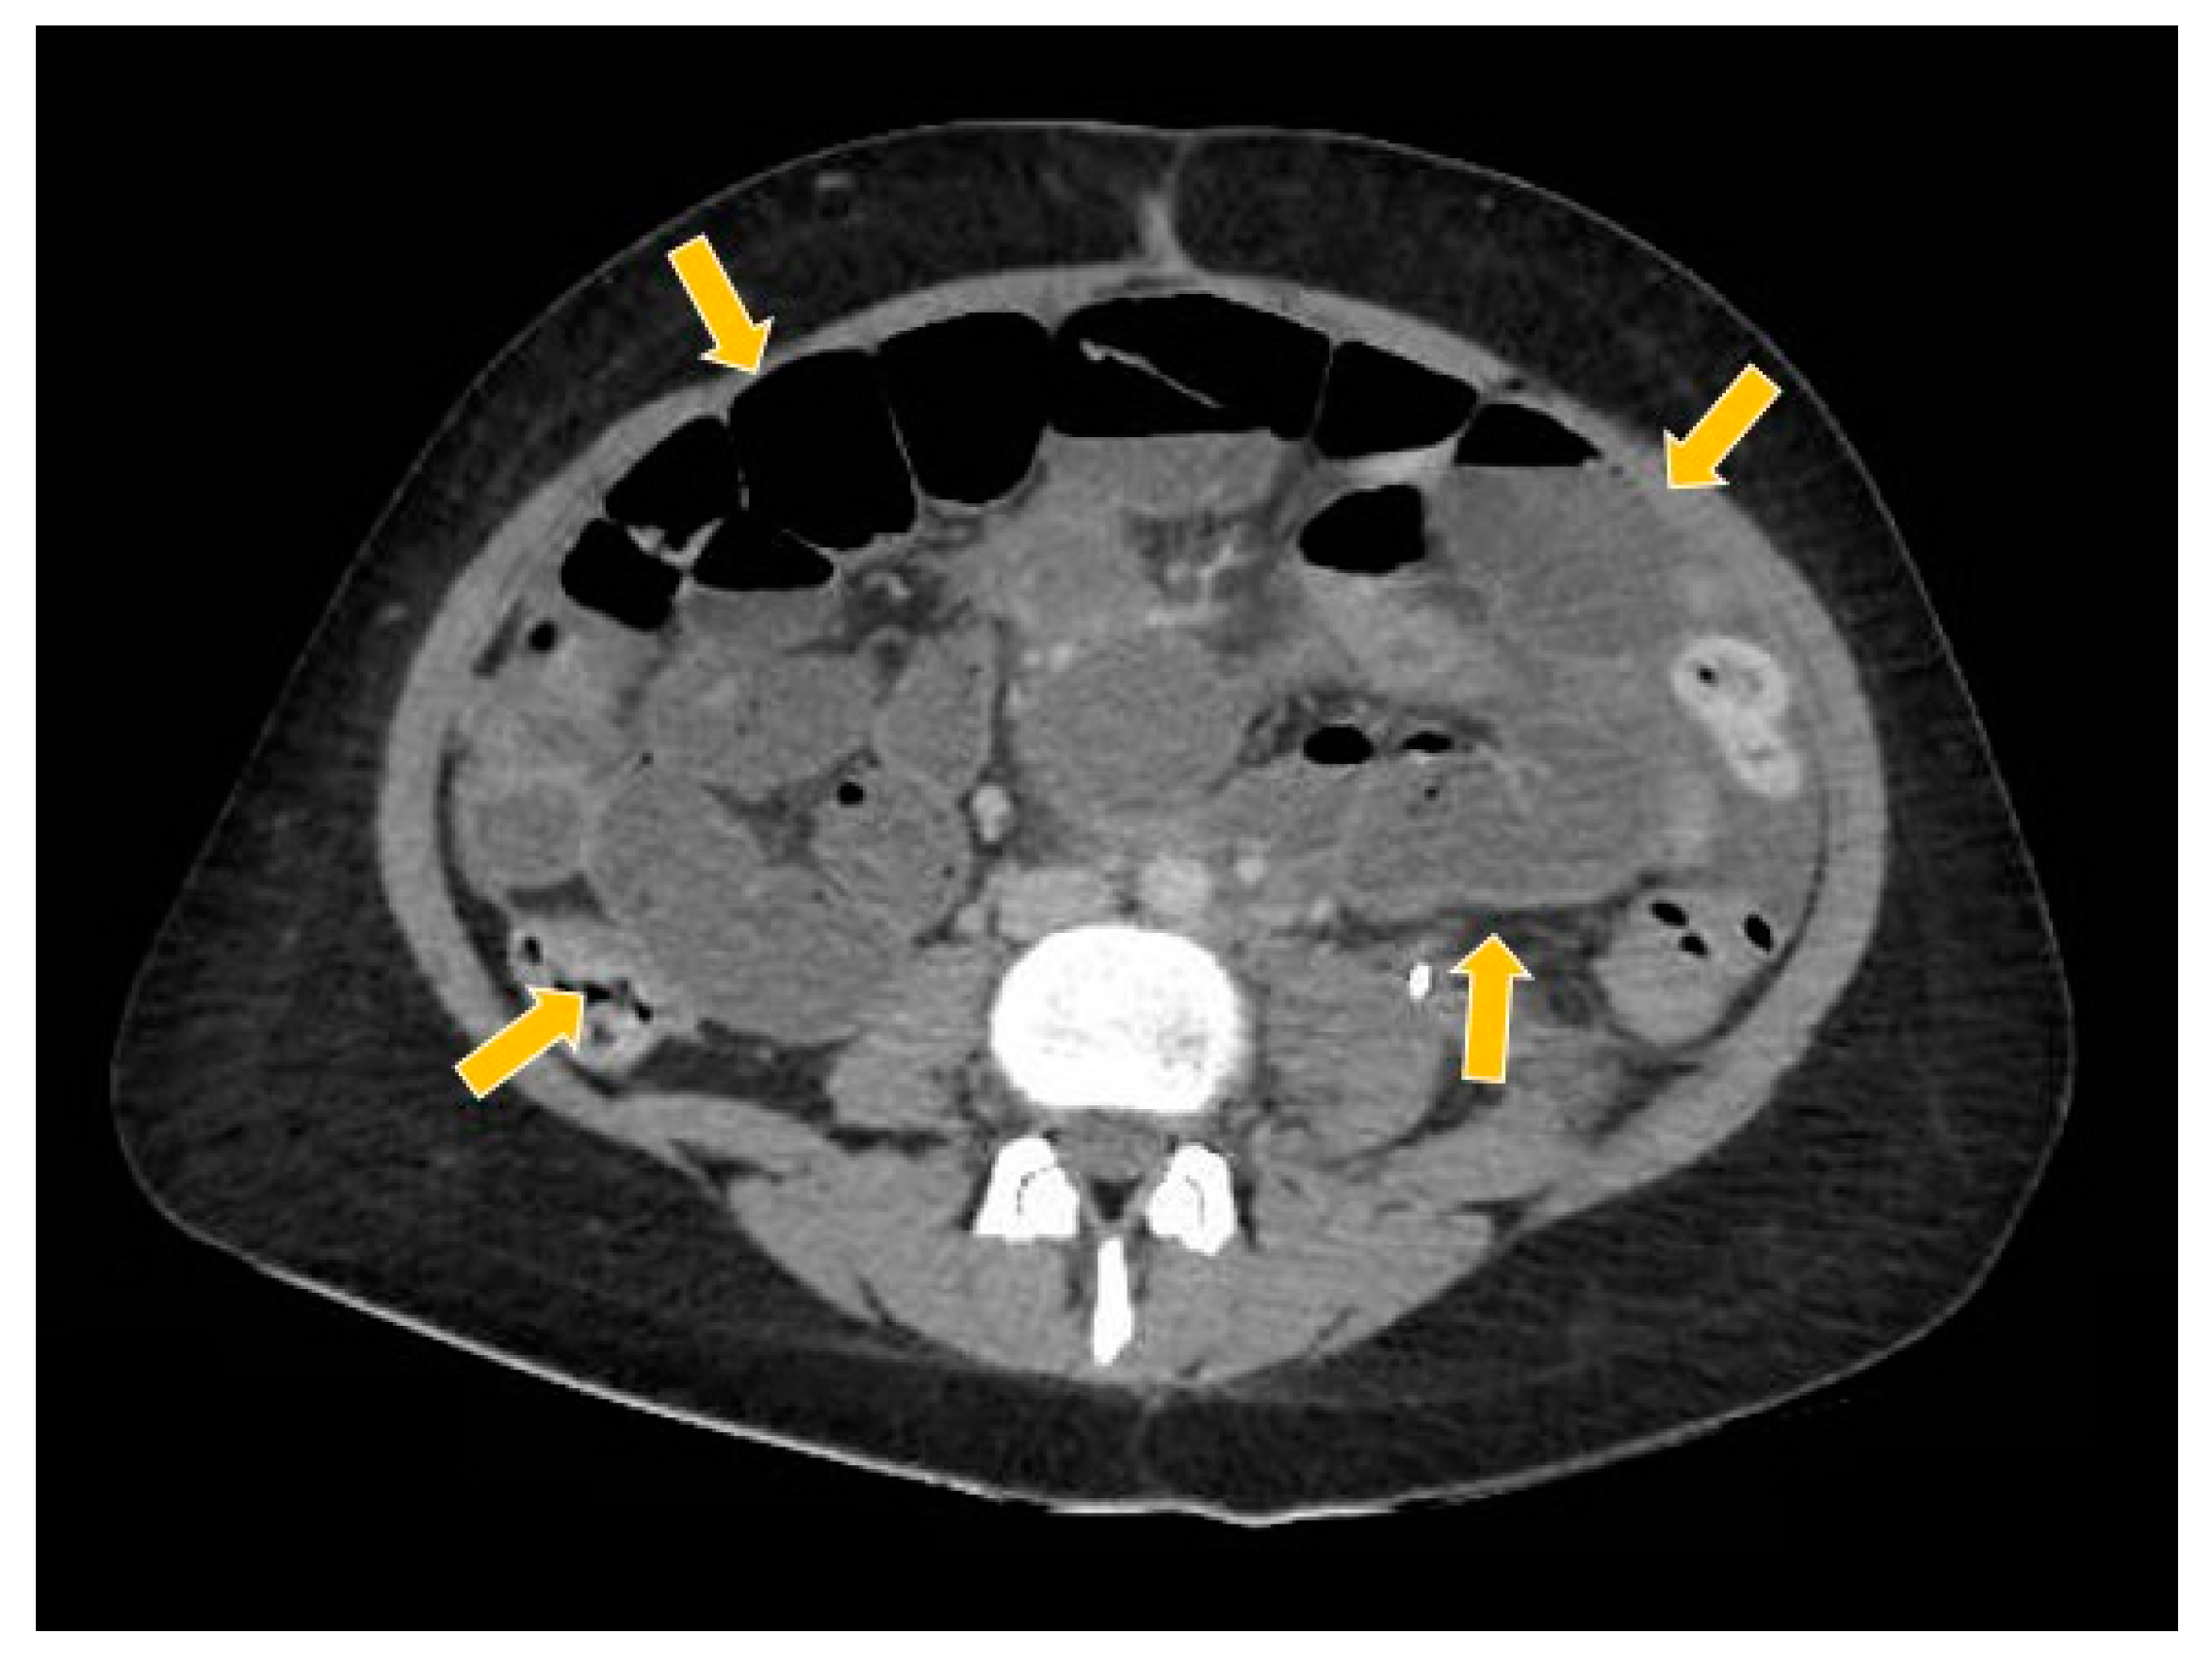

2. Case Report